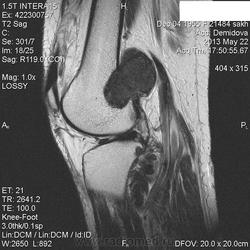

Вчера пациентка на рентгенографию коленного сустава приходила, нашла у нее изменения метадиафиза бедренной кости ( снимки затра выложу-не успеваю) , порекомендовала МРТ.Сегодня она у меня же и проходила исследование. ЗНО однозначно?Либо виллонодулярный синовит? Но разрушение кортикала ? за счет масс-эффекта? не пойму...

Сейчас вообще не пойму-образование , похоже, не из кости растет, а вызывает атрофию ее.Или мне кажется?

Остановилась на пигментном виллонодулярном синовите.

Никогда не видел сам вилонодулярного синовита, но мне кажется Вы правы, по сигнальным харатеристикам на него больше всего похожи изменения. И в большеберцовой кости изменения такие же.

С учетом тотальности поражения сустава по DICOM - без вариантов пигментный...

Написала про нерезкую деформацию и ( как мне показалось) кистовидные просветления со склеротическим ободком с признаками нарушения кортикального слоя на задней поверхности в нижней трети метадиафиза бедренной кости.По поводу вариантов были ГКО, АКК .Про пигмнтный синовит как-то даже мысли не было.Зато вспомнила, что пару месяцев назад была подобная коленка с менее выраженным дефектом кости в этом же месте бедра.Я тогда тоже порекомендовала МРТ, но больше пациента не видела.Ему 84 года , поэтому вряд ли родственники оплатят ему исслдование.А данная пациентка пришла на исследование сразу же, на другой день.